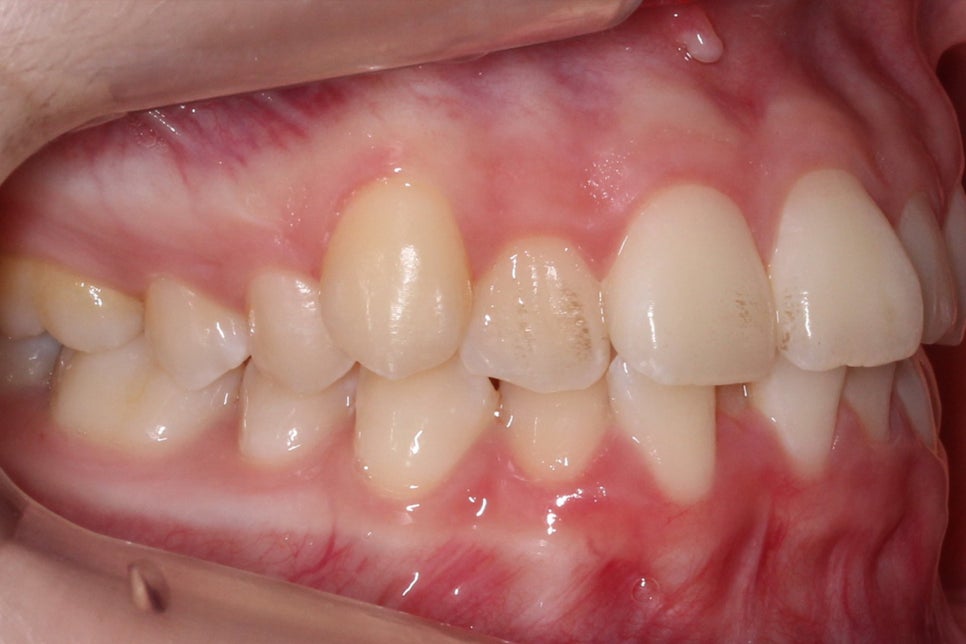

송곳니덧니 교정 후 전치부의 모습입니다.

치료전과 비교해보면 송곳니의 높이가

확연하게 달라진 것을 확인할 수 있는데요,

high canine로 인해 비교적 높은 위치에

맹출되어 있던 견치가 주변 치아들과

조화로운 위치로 교정된 모습입니다.

overbite 모습 역시 교정 후 아랫니가

가지런해지면서 전치부의 crowding이

해소된 모습을 확인할 수 있습니다.

deep bite나 open bite 증상 없이

바르게 교합되는 전치부의 모습이네요^^

2mm정도 덮는 상태가 이상적인 모습입니다.